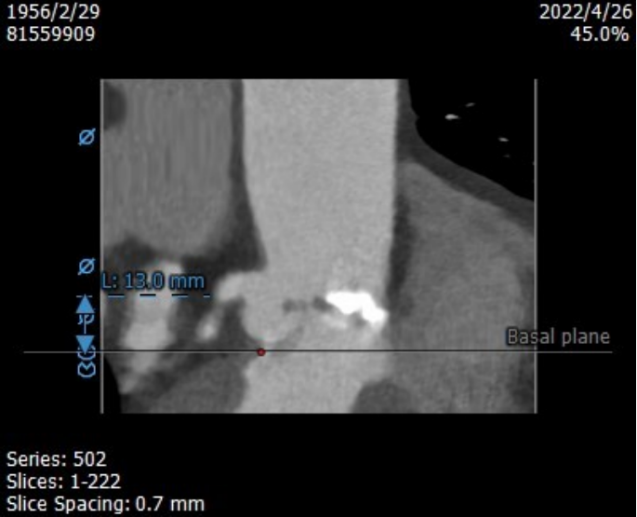

左冠开口高度13.0mm,右冠开口高度16.5mm,双侧冠脉开口未见明显附壁钙化,结合瓦氏窦宽度和瓣叶长度综合判断冠脉阻挡风险较低。

升主内径36.0mm,主动脉瓣环与水平面夹角39°,主动脉弓角与弓距可。